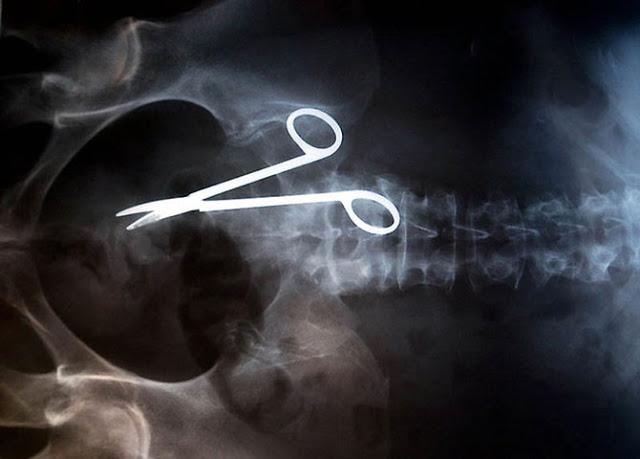

FOTOS: las cosas más insólitas que médicos encuentran gracias a los rayos X

Tan solo basta ver estas imágenes para sentir dolor. Y es que creer que estos objetos estén dentro de una persona viva, es casi imposible; sin embargo, lo único cierto es que todas ellas son reales.